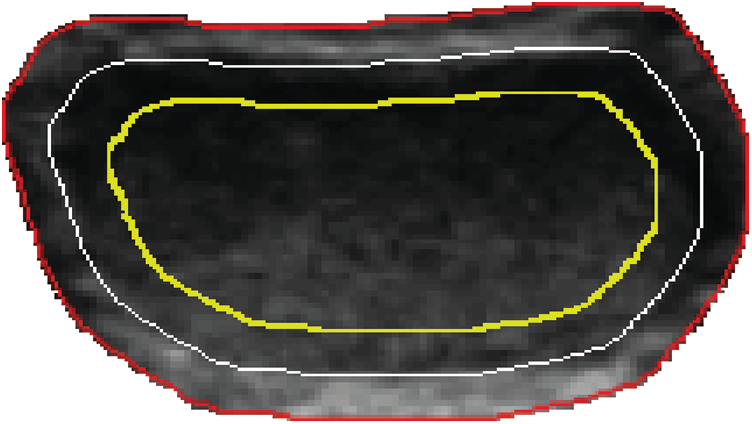

(6) The envelope and acoustic halo feature

The description of the edge feature of benign nodules generally involves envelope and acoustic halo. The quantification of edge features can be calculated through the gray distribution [23] at the adjacent areas of the nodules’ boundary. In the level set method, two strip areas which locate inside and outside of the nodule can be obtained. We respectively took a level set function −0.5, 0 and 0.5, among which the level set −0.5 corresponds to the nodule interior, level set 0 corresponds to the nodule boundary and level set 0.5 corresponds to the nodule exterior, as shown in Fig. 6.

Figure 6: Strip areas in and out of the tumor boundary

Assume that the numbers of pixel in the internal and external strip areas are